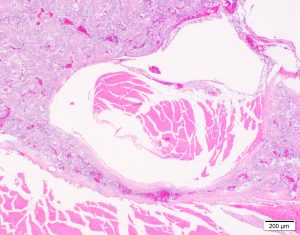

Variations of Medullary Bone

Discrete masses of medullary bone the efface and extend from the endosteal or periosteal surface. Wrap around and compress adjacent structures. Osteomas versus degenerative change? (I have seen only in Inca Doves – BT)